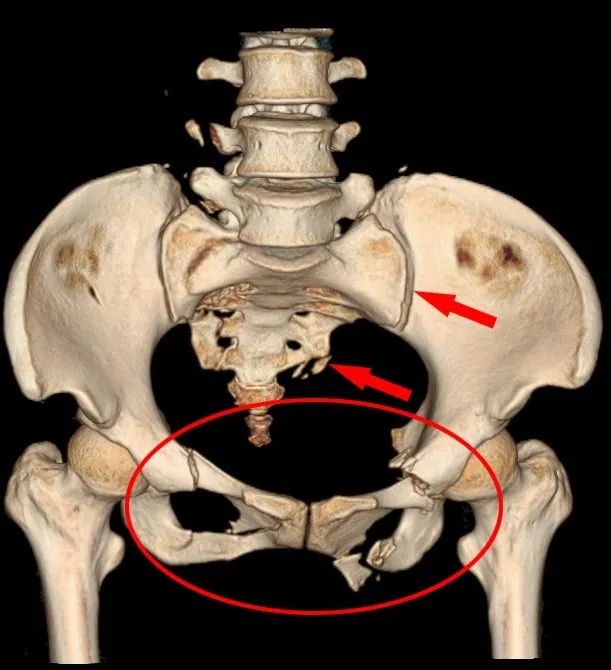

骨盆骨折、骶骨骨折、腰椎骨折、腹盆腔积血、肺挫伤、肋骨骨折、血压一度低至79/43mmHg……王女士骨盆遭受重创、多发骨折、失血性休克,凝血因子大量消耗丢失,血流动力学不稳定骨盆骨折死亡率高达60%以上。患者随时可能出现心跳停搏,病情极度危重!

▲CT前位显示骨盆、骶骨多发严重骨折

▲CT冠状面显示双侧骶髂髂关节增宽

“患者骨盆骨折双侧骶髂关节脱位,前环后环均不稳定,伴随右侧腰骶干神经损伤,髂外动静脉血管损伤,手术的难度高,极具挑战性。”荆门市人民医院创伤骨科主任施能兵介绍,科室立即实施加速康复外科(ERAS)临床路径管理,并利用3D打印技术还原骨折模型,制定个性化手术方案。